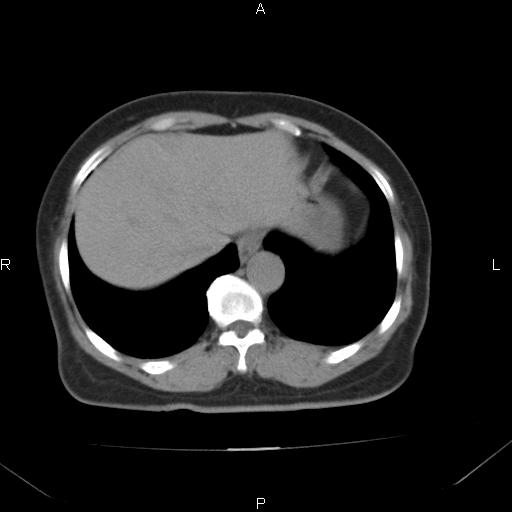

胸腺瘤

女、63Y 双眼睑下垂,早轻晚重。 胸腺瘤???

结果胸腺瘤